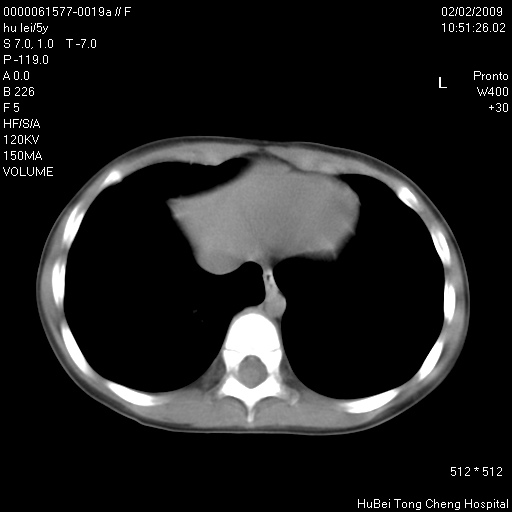

标题: PED1732:M5Y,右肺囊性占位!

患者:男,5。无明显不适,拍胸片考虑右肺囊肿。

行ct扫描,图象如下: